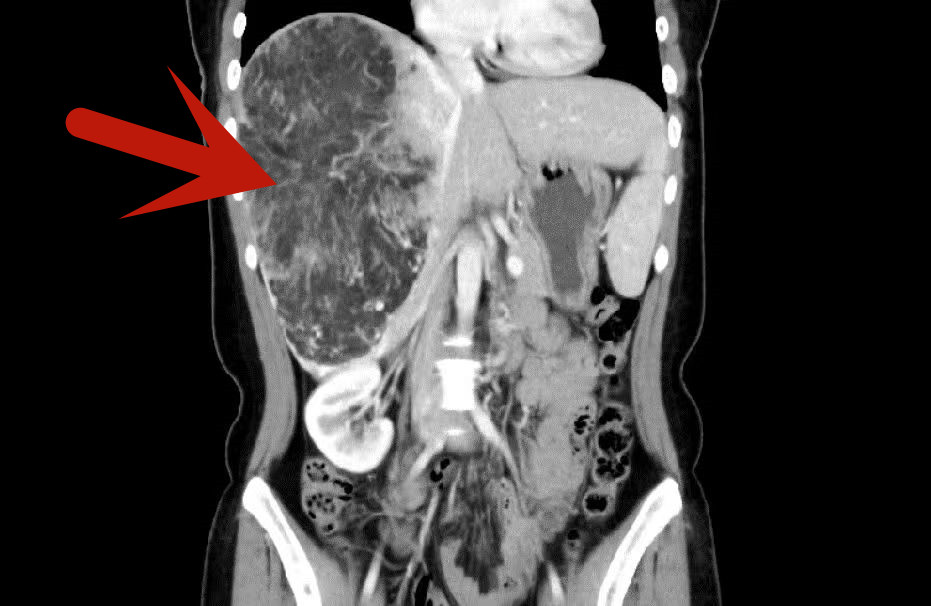

北京清华长庚医院2月8日电(通讯员 于悦超)近日,清华大学附属北京清华长庚医院肝胆胰外科团队,利用“达芬奇”机器人,为患者切除肝脏巨大血管平滑肌脂肪瘤,瘤体长21.3厘米、重量约5斤。

患者是位27岁的年轻女性,在一次体检中查出肝脏患有血管平滑肌脂肪瘤,当地影像提示肿瘤大小就已经达到了15.0cm×10.9cm×20.7cm。患者慕名到北京清华长庚医院肝胆胰外科就诊,先后问诊了李虎城主任医师和宋继勇副主任医师。“肝脏血管平滑肌脂肪瘤虽然是良性病变,但肿瘤增大后会压迫相关组织和脏器,并且有破裂和恶变的可能,需要手术切除。”宋继勇说,然而进一步的检查发现,患者的情况远不止肝脏占位这般简单,“我们发现患者还存在明显的门静脉海绵样变,肝门部血管增生严重,可能是由于肿瘤引起的血供增加导致的血管增生。”。

红色箭头处为肿瘤位置

术前,肝胆胰外科团队通过三维重建等,对患者肝功能储备、肝脏与周围血管关系等展开充分评估。如此大的肿瘤,传统的开腹切除是首选,然而,术前谈话时,手术团队了解到,患者对开腹手术后可能留下腹部较大的手术疤痕感到担忧,不愿接受传统的开腹手术,询问有无微创治疗的可能性。为了达成患者的意愿,宋继勇联合肝胆胰外科闫军副主任医师组织了科室会诊。“考虑肿瘤为良性,对周围的重要脉管无侵犯,从切除角度出发只需切除右半肝,而且在评估后患者的剩余肝体足够,符合微创治疗的手术指征,但是由于常规腹腔镜手术器械的局限性,无法达到肿瘤后部和底部,因此,机器人手术更为适合。”闫军说道,手术机器人系统具有清晰和放大的3D视野,加上能实时同步手术医生动作的机械手,可有6个方向的自由度,540°旋转,达到甚至超越人手的灵活性,在狭小的腹腔空间内可进行灵活、精准的操作。最终,经综合讨论,肝胆胰外科团队制订了经“达芬奇”机器人切除肿瘤的手术方案,然而,如此巨大肝脏肿瘤的切除,机器人也是在大出血风险的边缘试探,对操作者技艺发起极高挑战。